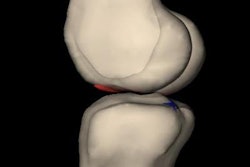

- Knee MRI for patients with anterior knee pain without mechanical symptoms or effusion, unless the patient shows no improvement after an appropriate functional rehabilitation program

- Knee arthroscopy as initial management for patients with degenerative meniscal tears and no mechanical symptoms

Dr. Thomas Magee, managing partner at NeuroSkeletal Imaging in Merritt Island, FL, said that as a radiologist he is not familiar with all of the symptoms that may warrant imaging, but a locking knee is a good indication that an MRI may be necessary.

"Then it is appropriate to order an MRI more quickly [rather] than later, the reason being that physical therapy in those scenarios won't work and may in fact be harmful," he said.